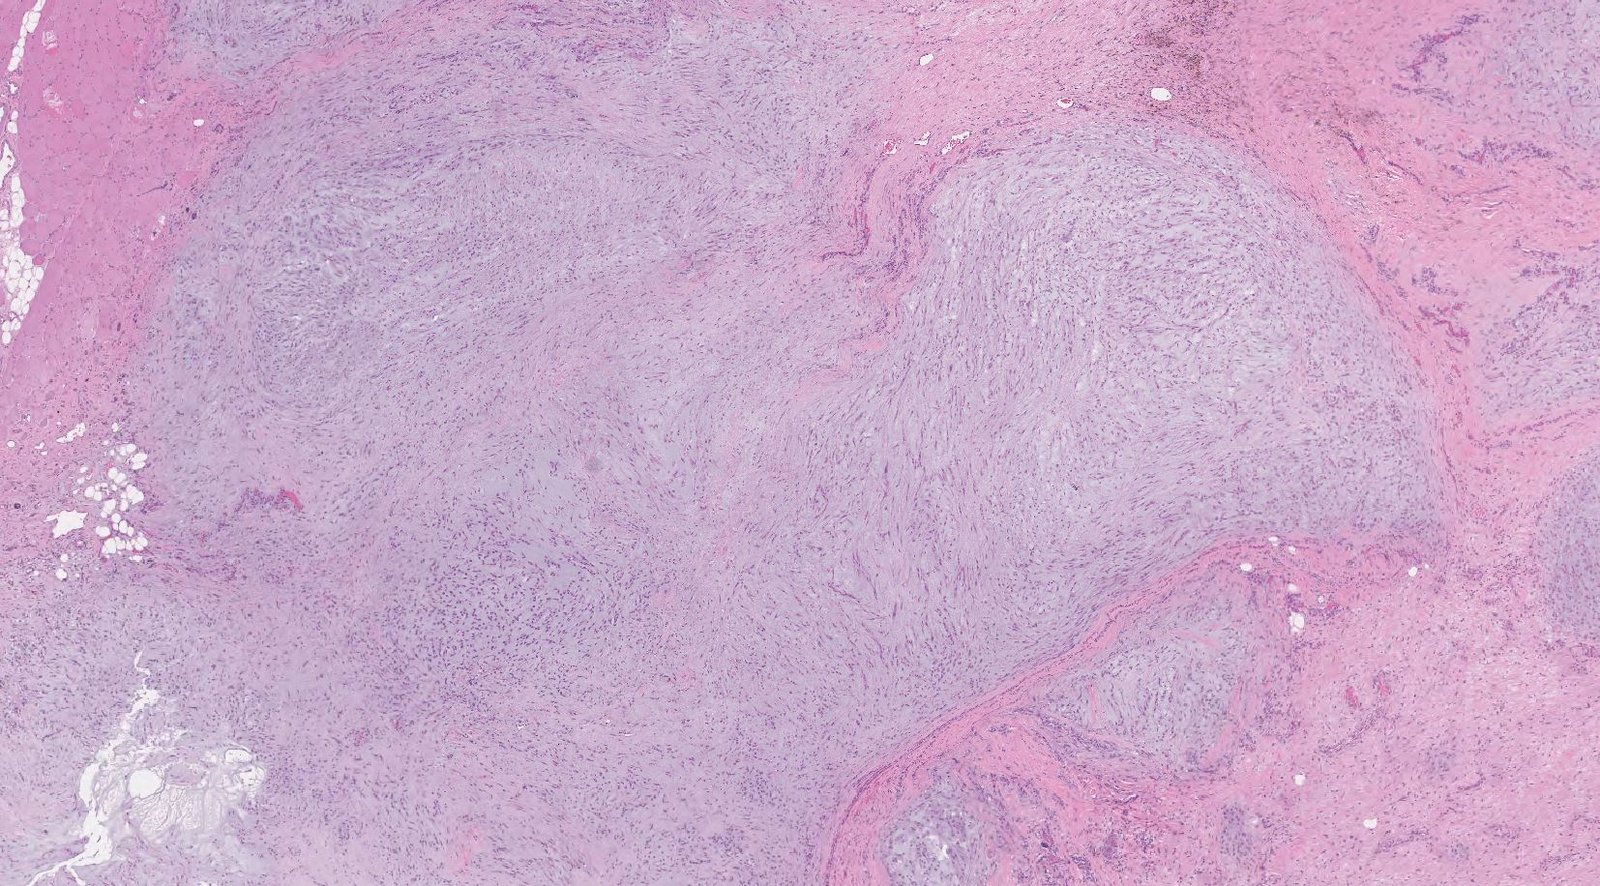

Case: ThighMass4

Final Diagnosis: